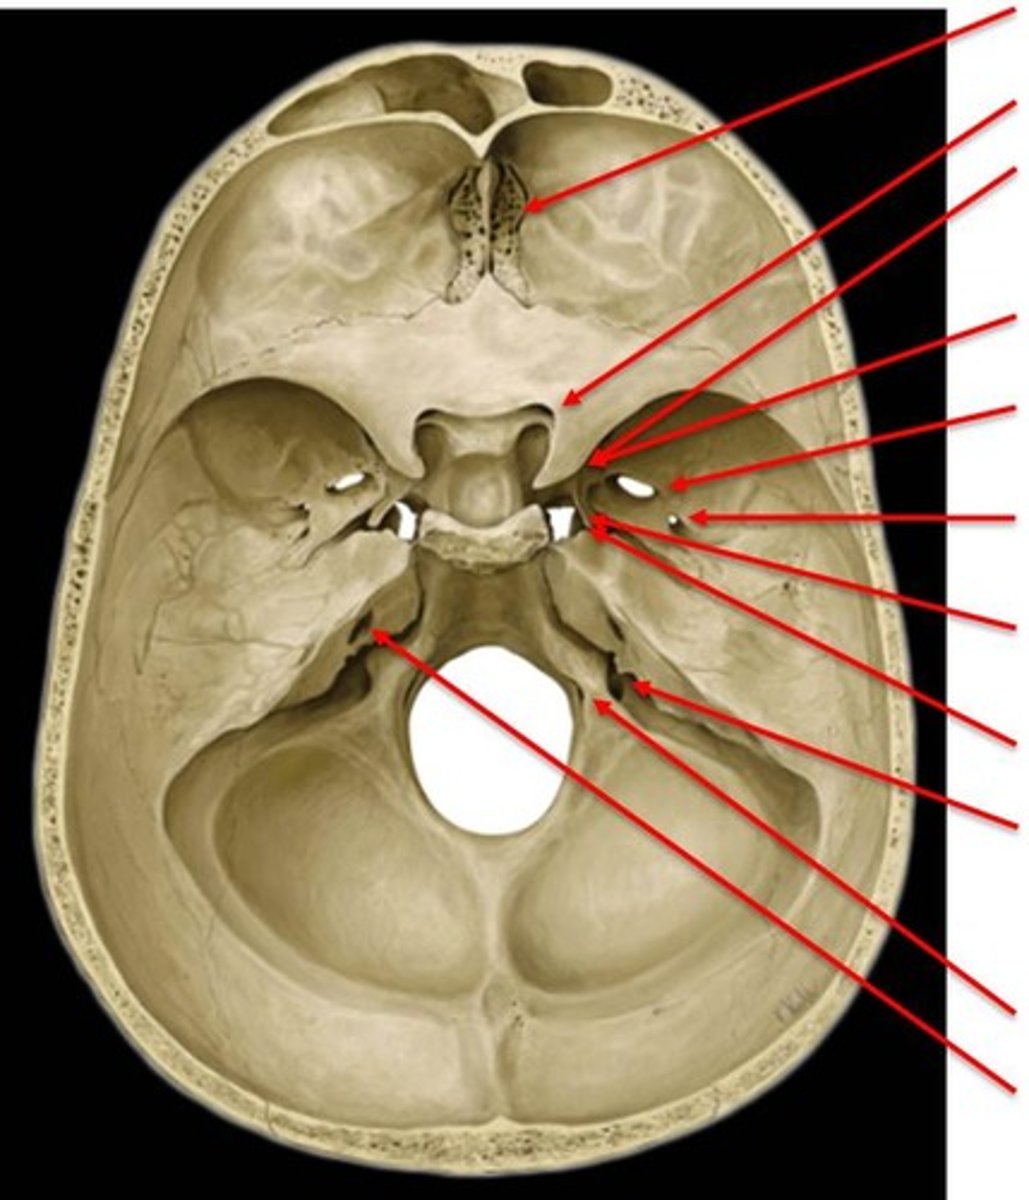

cranial fossa

three paired, tiered depressions (anterior, middle, posterior) on the internal base of the skull that cradle and protect the brain

anterior cranial fossa

part of the cranial fossa that contains openings for olfactory and ethmoidal structures & supports the frontal lobes

middle cranial fossa

part of the cranial fossa that is the major passageway for cranial nerves 2-6, and houses the temporal lobes & pituitary gland

posterior cranial fossa

part of the cranial fossa that is a major passageway for cranial nerves 7-12, and houses the cerebellum, pons, medulla, and the fourth ventricle

1. ethmoid

2. frontal

3. lesser wing of sphenoid

what 3 bones make up the anterior cranial fossa?

foramen cecum

hole that is typically closed, but may transmit the emissary vein

cribiform foramina

hole that transmits olfactory nerve filaments

ethmoidal foramina

hole that transmits ethmoidal nerves, arteries, and vessels

sella turcica

region of the middle cranial fossa that houses the pituitary gland

1. sphenoid (body/greater/lesser wings)

2. temporal bone (squamous & petrous)

what 2 bones make up the middle cranial fossa?

optic canal

hole that transmits the optic nerve (CN II) & the opthalmic artery

superior orbital fissure

opening that transmits cranial nerves III, IV, V1 and VI, and the superior opthalmic vein

foramen rotundum

hole that transmits the maxillary nerve (CN V2)

foramen ovale

hole that transmits the mandibular nerve (CN V3) and the accessory meningeal artery

foramen spinosum

hole that transmits the middle meningeal artery and vein

1. occipital

2. temporal (petrous part)

3. sphenoid (posterior)

what 3 bones make up the posterior cranial fossa?

foramen magnum

large opening at the based of the skull that transmits the spinal cord, vertebral arteries, and spinal accessory nerve (CN XI)

internal acoustic meatus

passage for facial (VII) and vestibulocochlear (CN VIII) nerves

jugular foramen

opening that transmits the internal jugular vein and cranial nerves IX, X, and XI

hypoglossal canal

hole that transmits the hypoglossal nerve (CN XII)